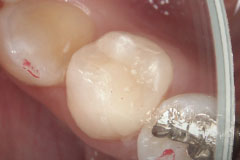

歯科用顕微鏡マイクロスコープを用いた

「見える・見せる」歯科治療

歯科用顕微鏡(マイクロスコープ)による歯科診療では根管治療(神経治療)や虫歯を削る場合に、より正確に必要な部分だけを削ること、さらに被せ物や詰め物をより正確に処置することができるようになります。また録画システムを用いて、治療内容やお口の状態を写真や動画でわかりやすく説明することができるため、しっかり情報を共有することができます。